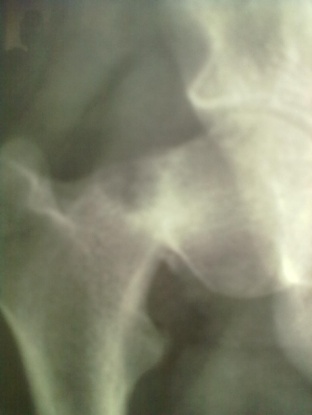

Sixteen patients of ununited fracture neck of femur (presenting late i.e. more than 3 weeks) in the children and adolescent were treated with quadratus femoris based muscle pedicle bone graft with internal fixation between 2004 to 2019. Pathological fracture, recent fracture and compound fracture were excluded from study. Mean age was 14.25 years (standard deviation 1.27 and range 12 to 16 years). Boys dominated our series (n=10 i.e. 62.50%) and right side was more commonly involved (n=12 i.e.75%). All of them were investigated for their fitness for spinal block or general anaesthesia. Steps of procedure including patient positioning, surgical procedure, provisional fixation and definitive fixation were discussed and documented. Radiographic evaluation included A-P View in 15 degree internal rotation, and Lateral view. Average delay in presentation was 5.88 weeks (range was 3-10 weeks). We had 02 transepiphyseal, 11 transcervical and 3 cervicotrochanteric fracture in our series. All the fractures were displaced and having some absorption of femoral neck.

Spinal block was used in the procedure. Prone position on fracture table with radiolucent top was used. Fracture site was exposed through posterior approach and sclerosed margins of the fragments were freshened. Fracture was reduced with appropriate neck shaft angle and fixed with Moors pin/ knowels pin or 4 mm /7mm partially threaded cancellous screws. Any rotation or tilt was corrected. The fixation was augmented with quadratus femoris muscle pedicle bone graft harvested from intertochateric crest area with a bone pedicle of length 2 cm, width 1 cm and depth 1 cm. The graft was secured to the proximal femoral head fragment with 3.5mm cortical screw or 4mm cannulated cancellous screw. Soft tissue closure was done over drain.